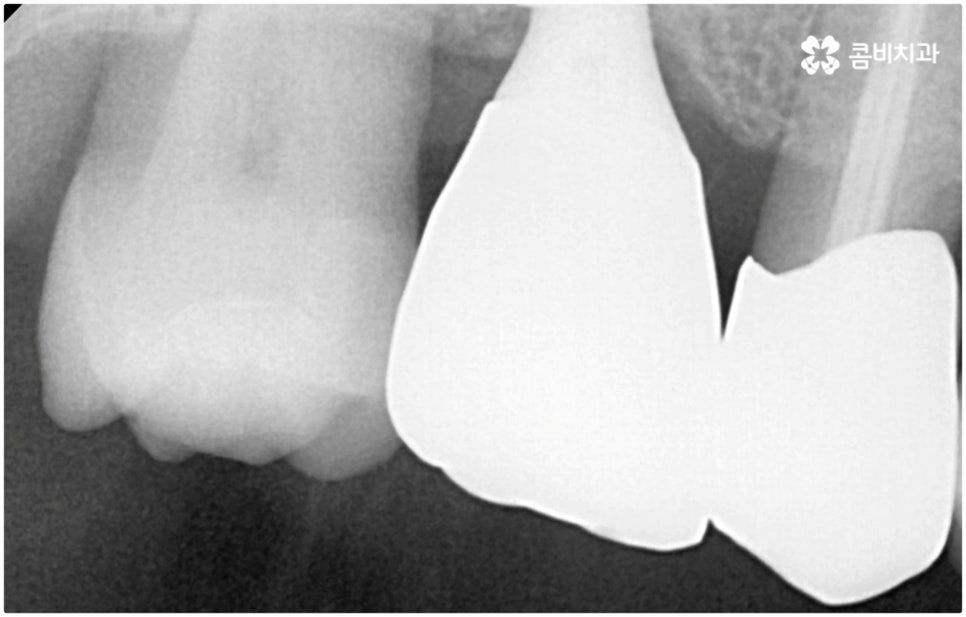

발치후 임플란트 즉시 식립 방식은 다른 임플란트와 달리 치아가 탈락한 빈 자리에 곧바로, 또는 조금 남아있던 뿌리를 뽑은 후 그 자리에 그대로 임플란트를 심기 때문에 공백 기간이 단축될 수 있고 임시치아 제작을 통해 해당 기간 동안 임시 틀니를 사용해야 하는 데서 오는 불편함 및 심미적인 어색함도 해결할 수 있어요. 또한 환자분들의 입장에서 마취 한 번에 발치와 식립 두 가지 과정이 함께 이뤄지기 때문에 통증과 두려움이 감소되고 치과에 내원해야 하는 횟수도 줄어들어 번거로움이 덜 할 수 있습니다.

치아가 빠진 순간부터 이를 받치고 있던 치조골이 서서히 흡수되기 시작하므로 영구치가 빠지고 나서 시간이 많이 지나게 되면 부족한 잇몸뼈 부분을 뼈이식으로 보충해 주는 과정이 추가적으로 들어가야 하지만 이미 뼈가 손상된 경우가 아니라면, 즉시 식립을 하면 그럴 필요가 없는 거예요. 또한 잇몸이 이미 내려앉은 후 수복을 하려면 잇몸 라인이 인위적으로 만들어질 가능성이 높아지는데 치조골 소실이 크게 일어나기 전에 임플란트를 심게 되면 주변 치아 및 잇몸과 보다 조화롭게 맞출 수 있어서 심미적인 부담도 덜 수 있어요.

발치후 임플란트 식립까지 회복 기간을 두지 않고 즉시 심게 되면 원래 치아가 있던 자리를 육안으로 확인한 후 그 자리에 곧바로 식립하므로 보다 정확한 위치를 잡을 수 있다는 장점도 있습니다. 하루 만에 식립과 임시치아까지 장착이 가능하여 간단한 식사도 할 수있다는 점에서 원데이 임플란트라고도 불리는 즉시 식립 방식은 지금까지 알아본 바와 같이 여러 장점을 가지고 있기 때문에 많은 분들이 선호하시고 있는데요.

하지만 여기서 주의하셔야 할 점은 누구나 발치후 임플란트 를 즉시 식립할 수 있는 것이 아니라 바탕이 되는 잇몸뼈의 양이 충분하고 기존에 염증과 같은 잇몸 질환이 없는 분들의 경우에만 이용할 수 있는 방법이기 때문에 3D CT 등 정밀 분석 기계로 환자분들의 상태를 정확하게 진단한 후에 결정해야 한다는 거예요.